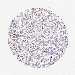

KIDNEY RENAL CLEAR CELL CARCINOMA (VALIDATION) - Interactive survival scatter ploti

The Survival Scatter plot shows the clinical status (i.e. dead or alive) for all individuals in the patient cohort, based on the same data that underlies the corresponding Kaplan-Meier plots. Patients that are alive at last time for follow-up are shown in blue and patients who have died during the study are shown in red.

The x-axis shows the expression levels (FPKM) of the investigated gene in the tumor tissue at the time of diagnosis. The y-axis shows the follow-up time after diagnosis (years). Both axes are complimented with kernel density curves demonstrating the data density over the axes. The top density plot shows the expression levels (FPKM) distribution among dead (red) and alive patients (blue). The right density plot shows the data density of the survived years of dead patients with high and low expression levels respectively, stratified using the cutoff indicated by the vertical dashed line through the Survival Scatter plot. This cutoff is automatically defined based on the FPKM cutoff that minimizes the p-score. The cutoff can be changed by dragging the vertical line or by entering a cutoff value in the square labeled "Current cut-off".

Under the Survival Scatter plot the p-score landscape (black curve; left axis) is shown together with dead median separation (red curve; right axis). Dead median separation is the difference in median mRNA expression between patients who have died with high and low expression, respectively. It is calculated as follows: median FPKM expression of dead patients with high expression - median FPKM expression of dead patients with low expression. This is intended to aid the user in visually exploring custom cutoffs and the associated p-scores and dead median separation.

Individual patient data is displayed and can be filtered by clicking on one or more of the category buttons on the top of the page. Categories describing expression level and patient information include: high, low, alive, dead, female, male and tumor stages. The scale of the x-axis can be toggled between linear and log-scale by clicking on the "x log" button. Mouse-over function shows TCGA ID, patient information and mRNA expression (FPKM) for each patient.

& Survival analysisi

Kaplan-Meier plots summarize results from analysis of correlation between mRNA expression level and patient survival. Patients were divided based on level of expression into one of the two groups "low" (under cut off) or "high" (over cut off). X-axis shows time for survival (years) and y-axis shows the probability of survival, where 1.0 corresponds to 100 percent.

POLR2I is not prognostic in Kidney Renal Clear Cell Carcinoma (validation)

Best expression cut offi

Based on the FPKM value of each gene, patients were classified into two groups and association between prognosis (survival) and gene expression (FPKM) was examined. The best expression cut-off refers the FPKM value that yields maximal difference with regard to survival between the two groups at the lowest log-rank P-value. Best expression cut-off was selected based on survival analysis .

When clicking on this number, the vertical dashed line indicating cut-off, the interactive survival plot, and the Kaplan-Meier curve will be adjusted to show results based on the best expression cut-off.

: 64.94

P scorei

Log-rank P value for Kaplan-Meier plot showing results from analysis of correlation between mRNA expression level and patient survival.

N/A

TCGA RNA samplesi

RNA-seq data is reported as average FPKM (number Fragments Per Kilobase of exon per Million reads), generated by the The Cancer Genome Atlas (TCGA) .

Normal distribution across the dataset is visualized with box plots, shown as median and 25th and 75th percentiles. Points are displayed as outliers if they are above or below 1.5 times the interquartile range. FPKM values of the individual samples are presented next to the box plot.

Average pTPM 82.9

Number of samples 100